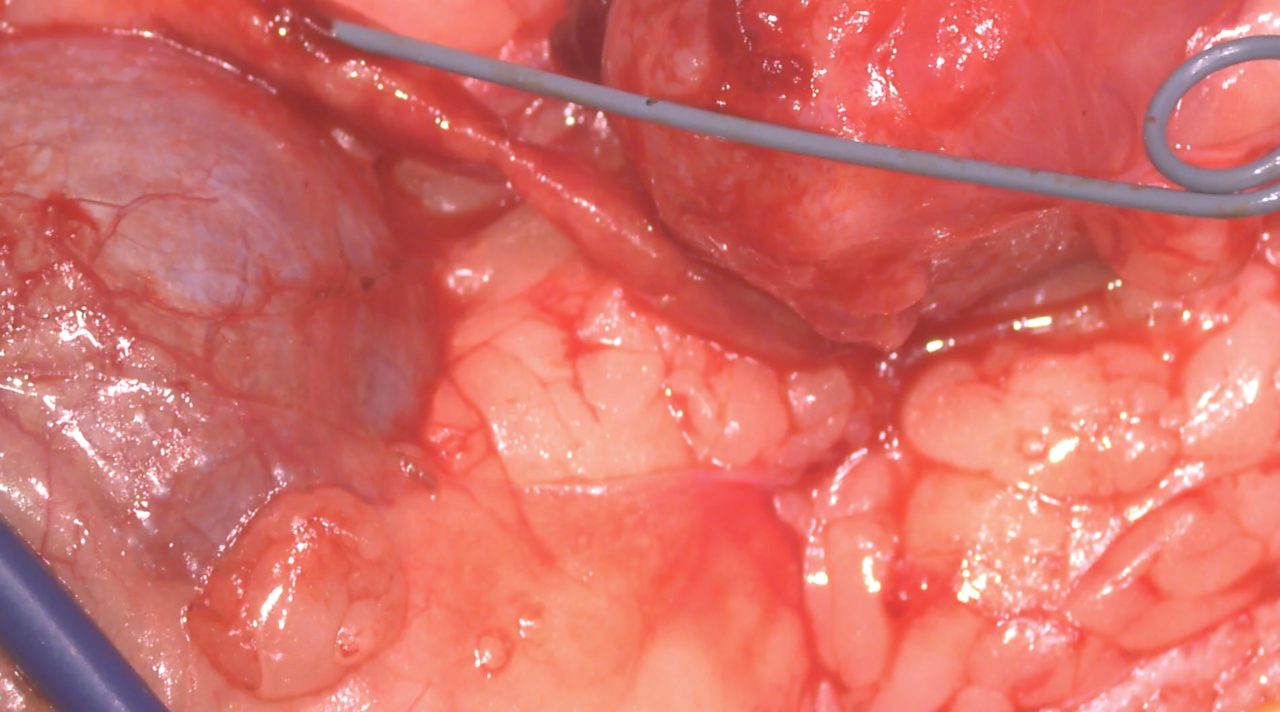

たった1mmの大きさの尿管結石でも猫の尿管を閉塞してしまうことがあります。血液検査、尿検査、超音波検査、無麻酔CT検査などで外科的に対応すべきか?詳しく評価します。閉塞してもすぐには腎盂の拡張はそれほど顕著ではありませんし、片側のみであれば血液検査に異常値が検出されないこともしばしばです。マイクロサージェリーで短尺ステントと尿管新吻合術で対応しました。通常はシュウ酸カルシウムであり溶解できないので非常に厄介です。